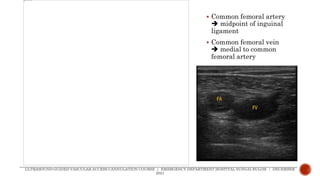

 Common femoral artery

 midpoint of inguinal

ligament

 Common femoral vein

 medial to common

femoral artery

 Common femoralartery  midpoint of inguinal ligament  Common femoral vein  medial to common femoral artery ULTRASOUND-GUIDED VASCULAR ACCESS CANNULATION COURSE | EMERGENCY DEPARTMENT HOSPITAL SUNGAI BULOH | DECEMBER 2021